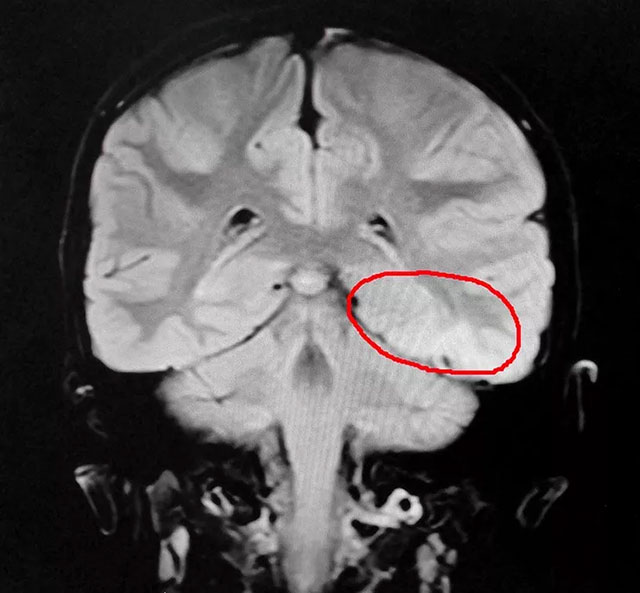

头颅MR平扫+增强+MRS+MRSI检查示:左颞叶(皮层区近小脑幕)病变,增强后未见明显强化,结合MRS,考虑良性病变,结合脑电、磁共振等多项检查终于在龙龙的大脑中确定了致痫区。

▲ 患儿癫痫病灶区域